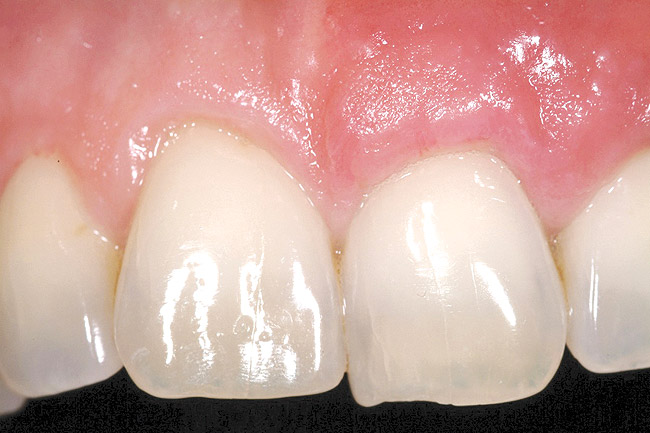

The 2-month postoperative view can be seen in Figure 13 through 15. Note the color match of the tissue, balance of the facial heights of contour, and zones of attached keratinized tissue present.

Figure 13  Case One The 2-month postoperative view, maxillary right.

Figure 13

Figure 14  Case One The 2-month postoperative view, maxillary anterior.

Figure 14

Figure 15  Case One The 2-month postoperative view, maxillary left

Figure 15